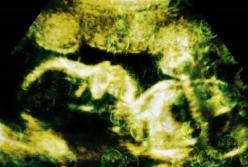

Ученые нашли микропластик в новорожденных младенцах

В ходе нового исследования микропластик был обнаружен в внутри человеческой плаценты, а также у новорожденных младенцев, передает FaceNews.